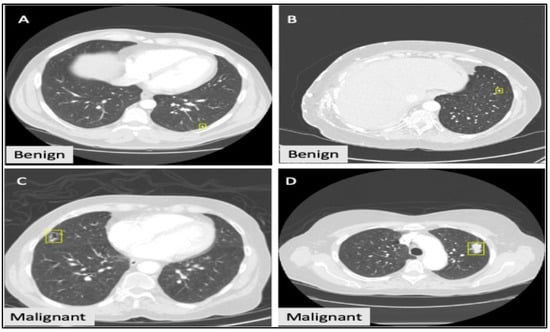

- Obstructive Pneumonia: This rectangle mark available in Figure 5 is a sign of a small lung nodule volume, which is due to distal collapse. This is mainly due to proximal bronchial blocking. It is combined with adenocarcinoma and squamous cell carcinoma. For a visual representation, it represents the cuneate or flabellate area with increased density. Among the descriptions of lung nodule signs, radiologists have concluded that the GGO, Cavity and Vacuoles, Lobulation, Bronchial Mucus Plugs, and Pleural Indentation represent the malignant lung nodule lesions. Air Bronchogram, Obstructive Pneumonia, and Calcification are classified as benign or malignant lesions. Figure 5 presents the sites of nine lung nodule signs in images in the database.